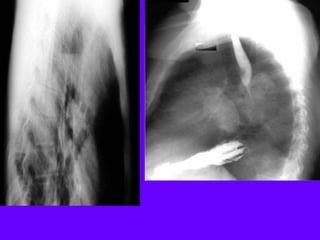

• Inhomogeneous

cardiac density:

Right half more

dense than left

• Density crossing

midline (right black

arrow)

• Right sided inlet to

outlet shadow

• Right para spinal line

(left black arrow)

• Barium swallow

below: Dilated

esophagus